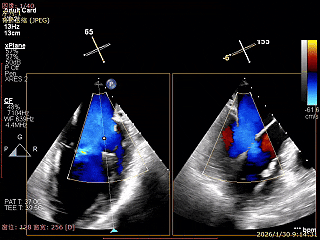

Bicomm切面看2区脱垂

上Color,可见反流主要来自于3区

X-Plane切面切1区未见明显异常

1区上Color,未见反流来源

X-Plane切面切2区可见前叶Flail

2区上Color,可见反流来源

X-Plane切面切3区可见前叶脱垂

3区上Color,可见反流来源

3D Enface 2区及3区前叶脱向左房

3D Enface 可见反流由2区3区从前后冲出